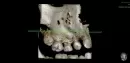

Ребенку 9,5 лет. Узкая верхняя челюсть. Наблюдается у ортодонта и носит пластинки с 5-ти лет. С апреля 2017 года (больше года назад) началась активная смена зубов. Ортодонт сказала на время приостановить ношение пластинок. На данный момент возникла непростая ситуация. На месте 2-х удаленных зубов клыка и 4-го зуба на верхней челюсти справа (качались) прорезался один постоянный клык и занял место двух удаленных молочных зубов. Места для прорезывания 4-го зуба нет. Я спросила ортодонта, когда же и куда будет прорезаться четвертый постоянный зуб. Ортодонт сказала, что по ортопантомограмме она четко не видит местонахождение этого зуба. Все зубы в одной куче сказала она. Чтобы четко разобраться, где какой зуб и понять дальнейшие шаги она сказала, сделать ребенку КТ 4-го и 5-го зуба и принести ей для расшифровки диск. Но после расшифровки диска она не сказала, ничего нового. Сказала только, что один зуб находится над другим, четвертый зуб находится в не выигрышном положении и упирается в корни прорезавшегося постоянного клыка. Она сказала, что нужно удалить 5-ый молочный зуб и посмотреть, какой зуб будет прорезаться на освободившееся место и в конце августа прийти для разговора о расширяющей верхнюю челюсть пластинке. На мои вопросы о том, как будут развиваться дальше события с 4-ым зубом я не получила четкого ответа от ортодонта.

Четвертый зуб расположен под углом и может давить на корни клыка, это чревато лигированием корней. Необходимо клык переместить мезиальнее и изготовить аппарат для дистализации. Для составления полноценного плана лечения необходим клинический осмотр и оценка диагностических моделей.